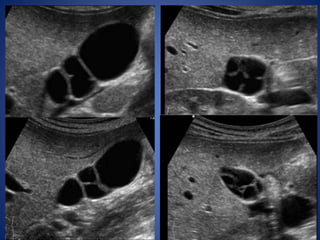

Multiseptate Gallbladder

The multiseptate gallbladder is a solitary gallbladder characterized

by multiple septa of various sizes internally and a faintly bosselated

surface externally.

The gallbladder is usually normal in size and position, and the chambers

communicate with one another by one or more orifices from fundus to

cystic duct.

These septations lead to stasis of bile and gallstone formation.

On ultrasound studies, multiple communicating septations and locules

are seen bridging the gallbladder lumen.

The sonographic differential diagnoses are desquamated gallbladder

mucosa and hyperplastic cholecystoses.